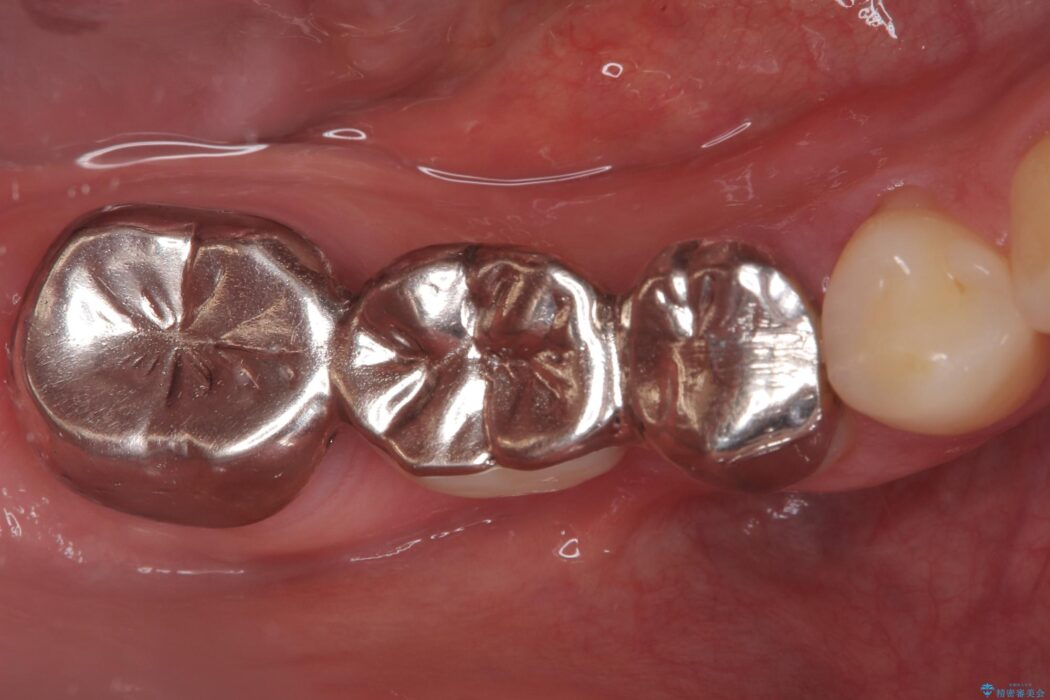

右下奥歯の5・6・7番に装着されていたブリッジの不具合を主訴にご来院された患者様です。

ブリッジは汚れが溜まりやすく、土台となる歯への負担も大きいため、患者様の希望に合わせそれぞれの歯をインプラント治療で独立させる治療計画を立てました。

ブリッジを外し、欠損している6番にインプラントを埋入。土台となっていた5番と7番は、セラミッククラウンで修復。